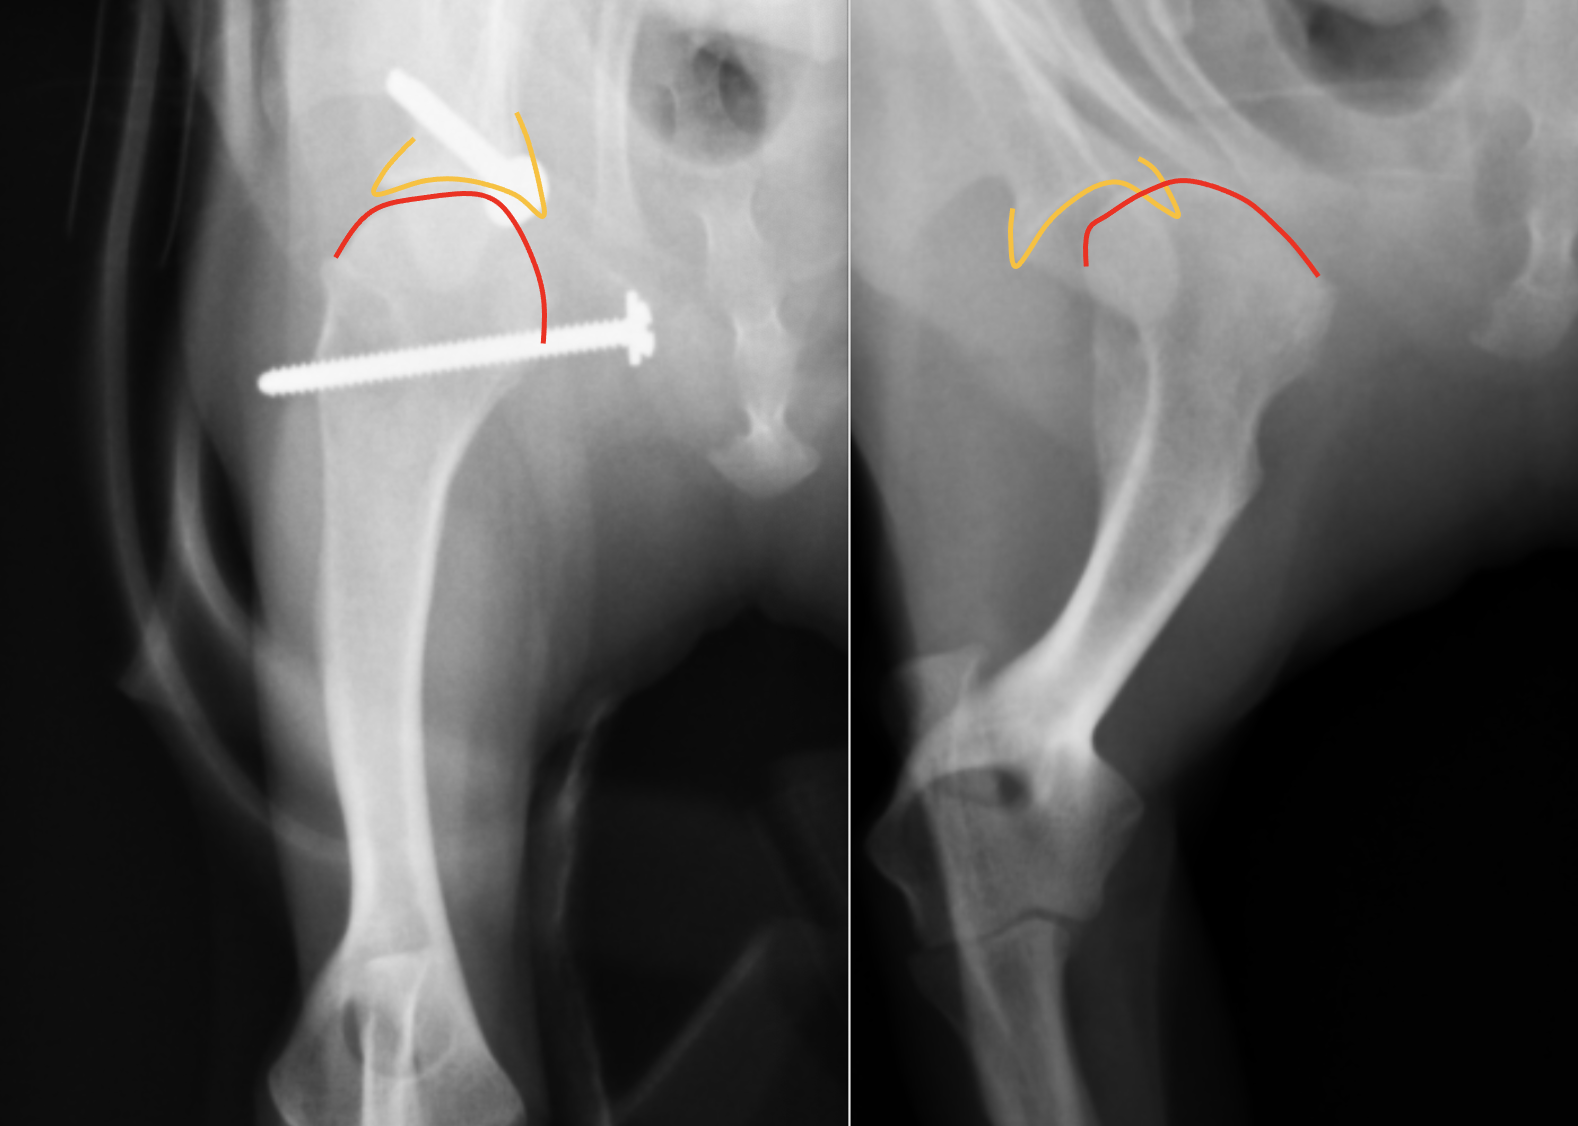

別の症例です。右が術前、左が術後のレントゲンです。分かりやすく肩甲骨と上腕骨に線を引くと・・・・

オレンジのラインが肩甲骨で、赤いラインが上腕骨頭です。右の術前は全くあっていなかった関節が、左の術後にはピッタリとあっているのがわかると思います。今回は前回のスクリューにプラスして、肩甲骨にもアンカーを入れ、糸による靭帯の強化をおこなっています。